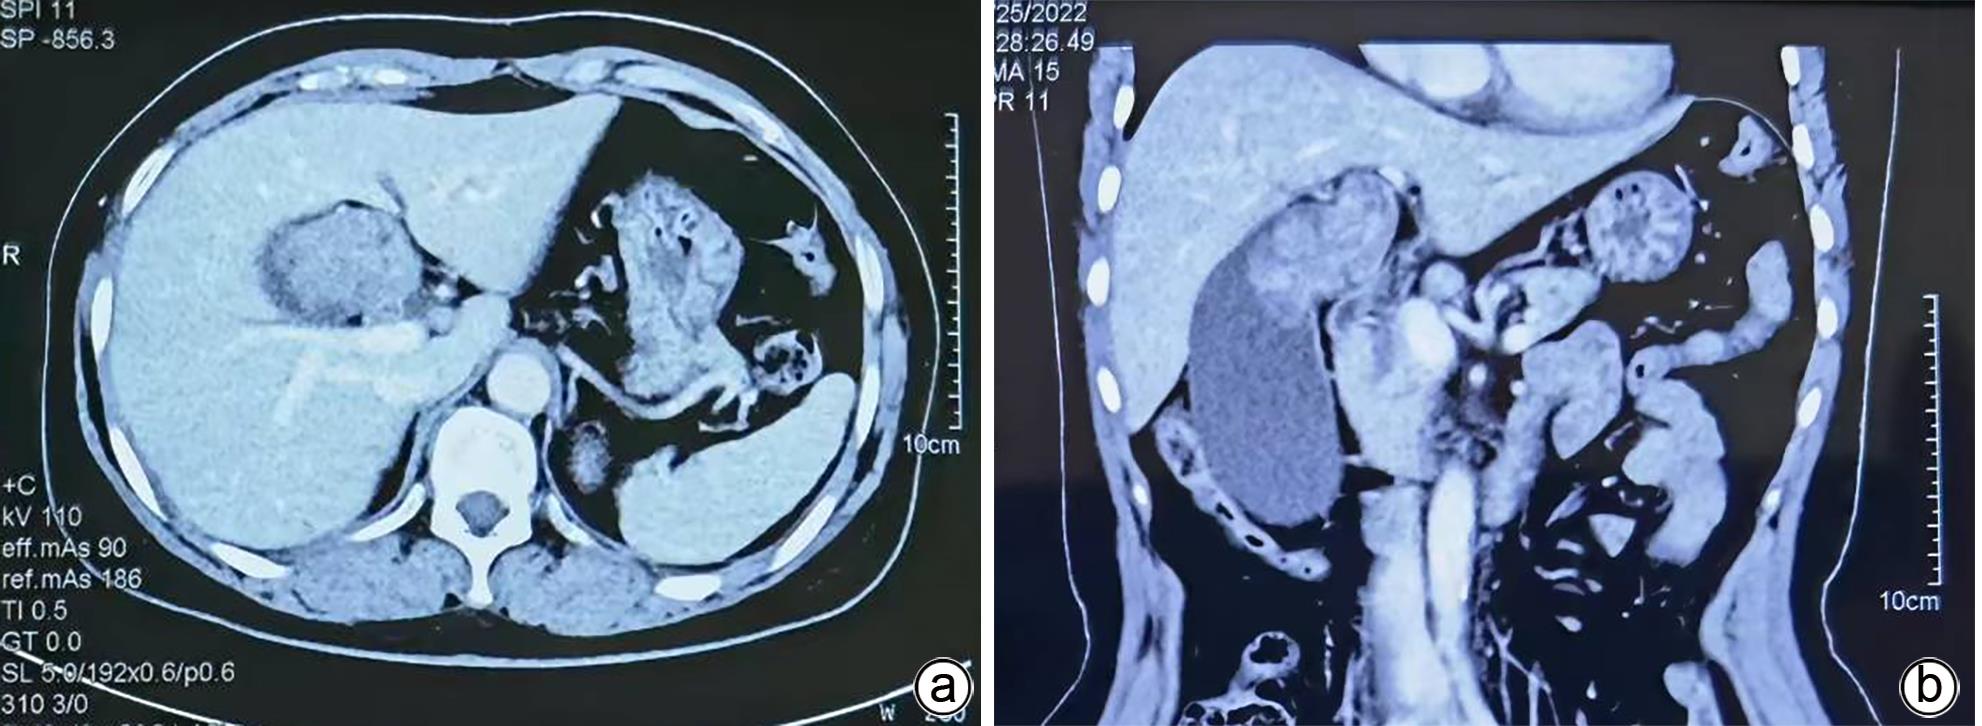

1例胆囊肿物患者,曾出现一过性黄疸,经腹部超声、增强CT、MRCP及PET-CT检查,均诊断为胆囊癌。手术探查见胆囊增大,胆囊颈部肿物挤压肝门部,但没有肿瘤侵犯表现,肝脏未见肿瘤转移征象,仅为患者行胆囊切除术。病理诊断为胆囊管状腺瘤,未见癌变。本病例特点是胆囊肿瘤巨大,影像未见肿瘤边缘浸润,病理未见恶变。